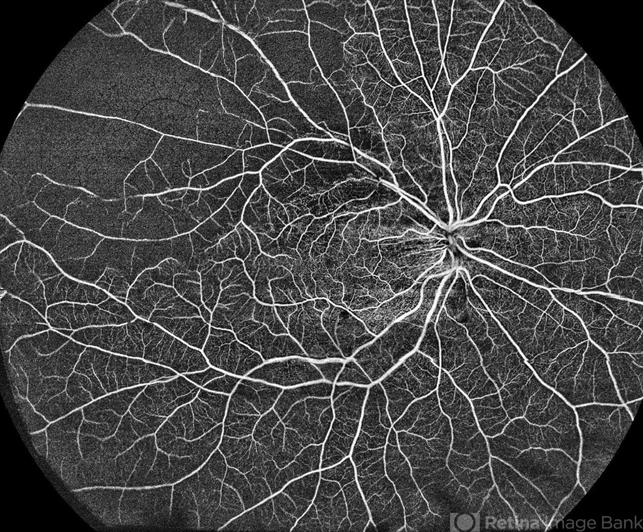

- retina, branch retinal vein occlusion (BRVO), nonproliferative diabetic retinopathy

TOWARDPI BMIZAR – 400KHZ FULL RANGE SS-OCTA - Description

- Ultra-Widefield OCT Angiography of a 77-year-old woman with ischemic occlusion of the superior temporal branch of the central retinal vein with non-proliferative diabetic retinopathy.